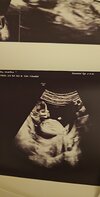

Tak - to na pewno chłopiec lub dziewczynka ;-)

Jeśli chodzi o kształt czaszki to bardziej skłaniam się do chłopczyka.A nie widać dokładnie jeszcze ploci ?

Rozumiem narzeczony ta nóżka sugerował się ze chłopiec co prawda mamy juz dwójkę chlopcow ja wręcz się nastawiam na dziewczynkę tym razemNa tym zdjęciu nie ma wyrostka płciowego tylko fragment nóżki . Nic nie widać

Trzymam kciuki za córeczkę , na kolejnym usg już powinno się udać zobaczyć jaka płećRozumiem narzeczony ta nóżka sugerował się ze chłopiec co prawda mamy juz dwójkę chlopcow ja wręcz się nastawiam na dziewczynkę tym razem![]()